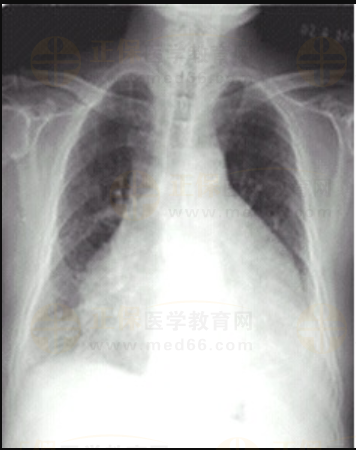

03卷-5.女性,63歲,咳嗽、咳痰、胸悶2月,伴下肢浮腫4天。診斷

A.靴形心

C.普大型心臟

D.梨形心

【該題針對(duì)“ X線-心臟增大(二尖瓣型、主動(dòng)脈型和普大型) ”知識(shí)點(diǎn)進(jìn)行考核】